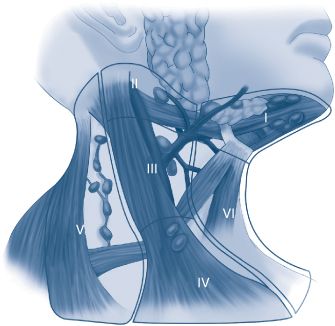

The regional lymphatic drainage of the neck is divided into seven levels. These levels allow for a standardized format for radiologists, surgeons, pathologists, and radiation oncologists to communicate concerning specific sites within the neck (Fig. 18-3). (See Schwartz 9th ed., p 503.) The levels are defined as the following:

Level I—the submental and submandibular nodes

Level Ia—the submental nodes; medial to the anterior belly of the digastric muscle bilaterally, symphysis of mandible superiorly, and hyoid inferiorly

Level Ib—the submandibular nodes and gland; posterior to the anterior belly of digastric, anterior to the posterior belly of digastric, and inferior to the body of the mandible

Level II—upper jugular chain nodes

Level IIa—jugulodigastric nodes; deep to sternocleidomastoid (SCM) muscle, anterior to the posterior border of the muscle, posterior to the posterior aspect of the posterior belly of digastric, superior to the level of the hyoid, inferior to spinal accessory nerve (CN XI)

Level IIb—submuscular recess; superior to spinal accessory nerve to the level of the skull base

Level III—middle jugular chain nodes; inferior to the hyoid, superior to the level of the cricoid, deep to SCM muscle from posterior border of the muscle to the strap muscles medially

Level IV—lower jugular chain nodes; inferior to the level of the cricoid, superior to the clavicle, deep to SCM muscle from posterior border of the muscle to the strap muscles medially

Level V—posterior triangle nodes

Level Va—lateral to the posterior aspect of the SCM muscle, inferior and medial to splenius capitis and trapezius, superior to the spinal accessory nerve

Level Vb—lateral to the posterior aspect of SCM muscle, medial to trapezius, inferior to the spinal accessory nerve, superior to the clavicle

Level VI—anterior compartment nodes; inferior to the hyoid, superior to suprasternal notch, medial to the lateral extent of the strap muscles bilaterally

Level VII—paratracheal nodes; inferior to the suprasternal notch in the upper mediastinum

FIG. 18-3. Levels of the neck denoting lymph node bearing regions.